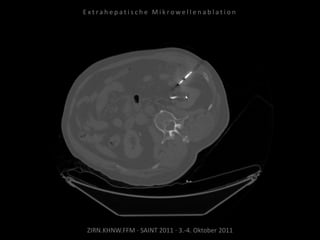

Patient: Weiblich, 82 Jahre

Diagnose: Z.n. Nieren-Ca rechts,

ausgedehnte retroperitoneale

Lymphknotenmetastasen links mit

Verdrängung der linken Niere.

Ausgangsbildgebung:

CT vom 04.09.2009

CT vom 29.12.2009

Situation:

Z.n. Nephrektomie rechts, nun

Verlagerung des linken Nierenstiels

durch retroperitoneale Metastasen und

hierdurch Gefährdung der verbliebenen

Niere.

Ziel:

Organerhalt durch Stoppen des

Tumorwachstums, idealerweise

Verminderung der Tumormasse. Kein

kurativer Ansatz.

Indikation zur MWA:

Exakte Positionierbarkeit und definiertes

Wirkvolumen, daher Tumordestruktion

unter Schonung der Nachbarstrukturen.

Bildgebung vor MWA:

CT 17.02.2010

Ablation am 04.03.2010:

3 Nadelpositionen.

Verlaufskontrolle:

CT 24.06.2010

Regredienz des abladierten

Tumorgewebes.

CT 15.09.2010

Weitere Regredienz des abladierten

Resultat:

Abladierte Lymphknotenmetastasen

deutlich regredient, Gefahr für die

verbliebene Niere gebannt.

Fazit:

Die Mikrowellenablation kann außerhalb

eines kurativen Ansatzes zur

Organerhaltung durch Reduzierung von

Tumormasse eingesetzt werden.